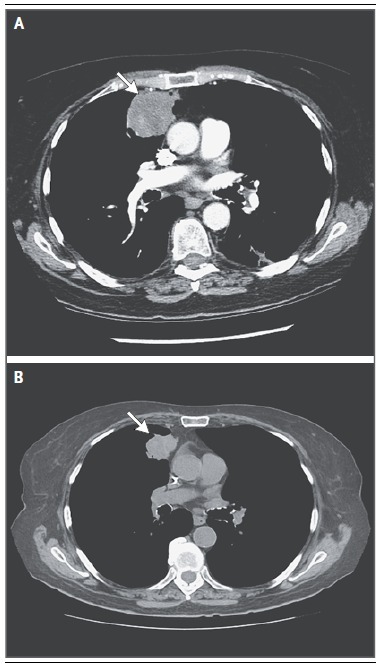

对于另外 75% 的患者,免疫组化结果不能明确其诊断。图 4 显肝脏巨大肿块,影像学提示胆管癌。

图 4 原发灶不明的转移癌与胆管癌的鉴别。由于原发灶不明的转移癌中肝脏受累很常见,与胆道肿瘤的鉴别则显得尤为重要,尤其伴或不伴卫星结节,有大的孤立肝脏肿块的患者。MRI 多相扫描显示延长期强化, 提示胆管癌(箭头处)。免疫组化检测没有诊断价值,应避免做多种分子印迹检测。

这些病例的免疫组化结果往往是非特异性的,而胆管癌通常不认为是原发灶不明的转移癌。免疫组化检测结果非特异性的患者可根据临床病理选择以铂类为基础的方案,也可采取包括组织来源分子分析和新一代测序在内的基因组学研究。许多肿瘤缺乏具体而有效的药物,而且大多数肿瘤的治疗方案也有重叠。然而,随着普通已知肿瘤新的治疗方法的研发,分子诊断工具可能成为原发灶不明的转移癌的基石。